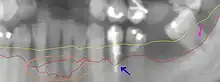

| Radiograph showing bone loss between the two roots of a tooth (black region). The spongy bone has receded due to infection under tooth, reducing the bony support for the tooth. | |

| Diagnostic method | Dental examination, X-rays[1] |

Periodontal disease is generally due to bacteria in the mouth infecting the tissue around the teeth.[5] Factors that increase the risk of disease include smoking,[4] diabetes, HIV/AIDS, family history, high levels of homocysteine in the blood and certain medications.[1] Diagnosis is by inspecting the gum tissue around the teeth both visually and with a probe and X-rays looking for bone loss around the teeth.[1][9]

- Amount and percentage bone loss radiographically